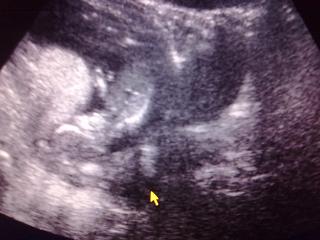

Minden rendben van!

BDP: 2,30 cm

CRL: 62,9 mm

NT: norm. , 1,6 mm

Babu éppen alukált :)